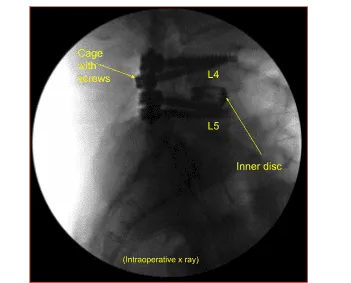

Se abrió una pequeña BMP en preparación para la fusión. La descompresión de revisión de L4-5 se realizó con laminectomía inferior de L3. El hueso se utilizaba para autoinjertos locales. Se realizó una descompresión completa de las L4 y L5 de la izquierda y derecha con curettes seguidas de punzón Kerrison. Se podía lograr una descompresión completa. Se colocó un nuevo tornillo de ajuste en la L4 izquierda y se apretó de la manera habitual.